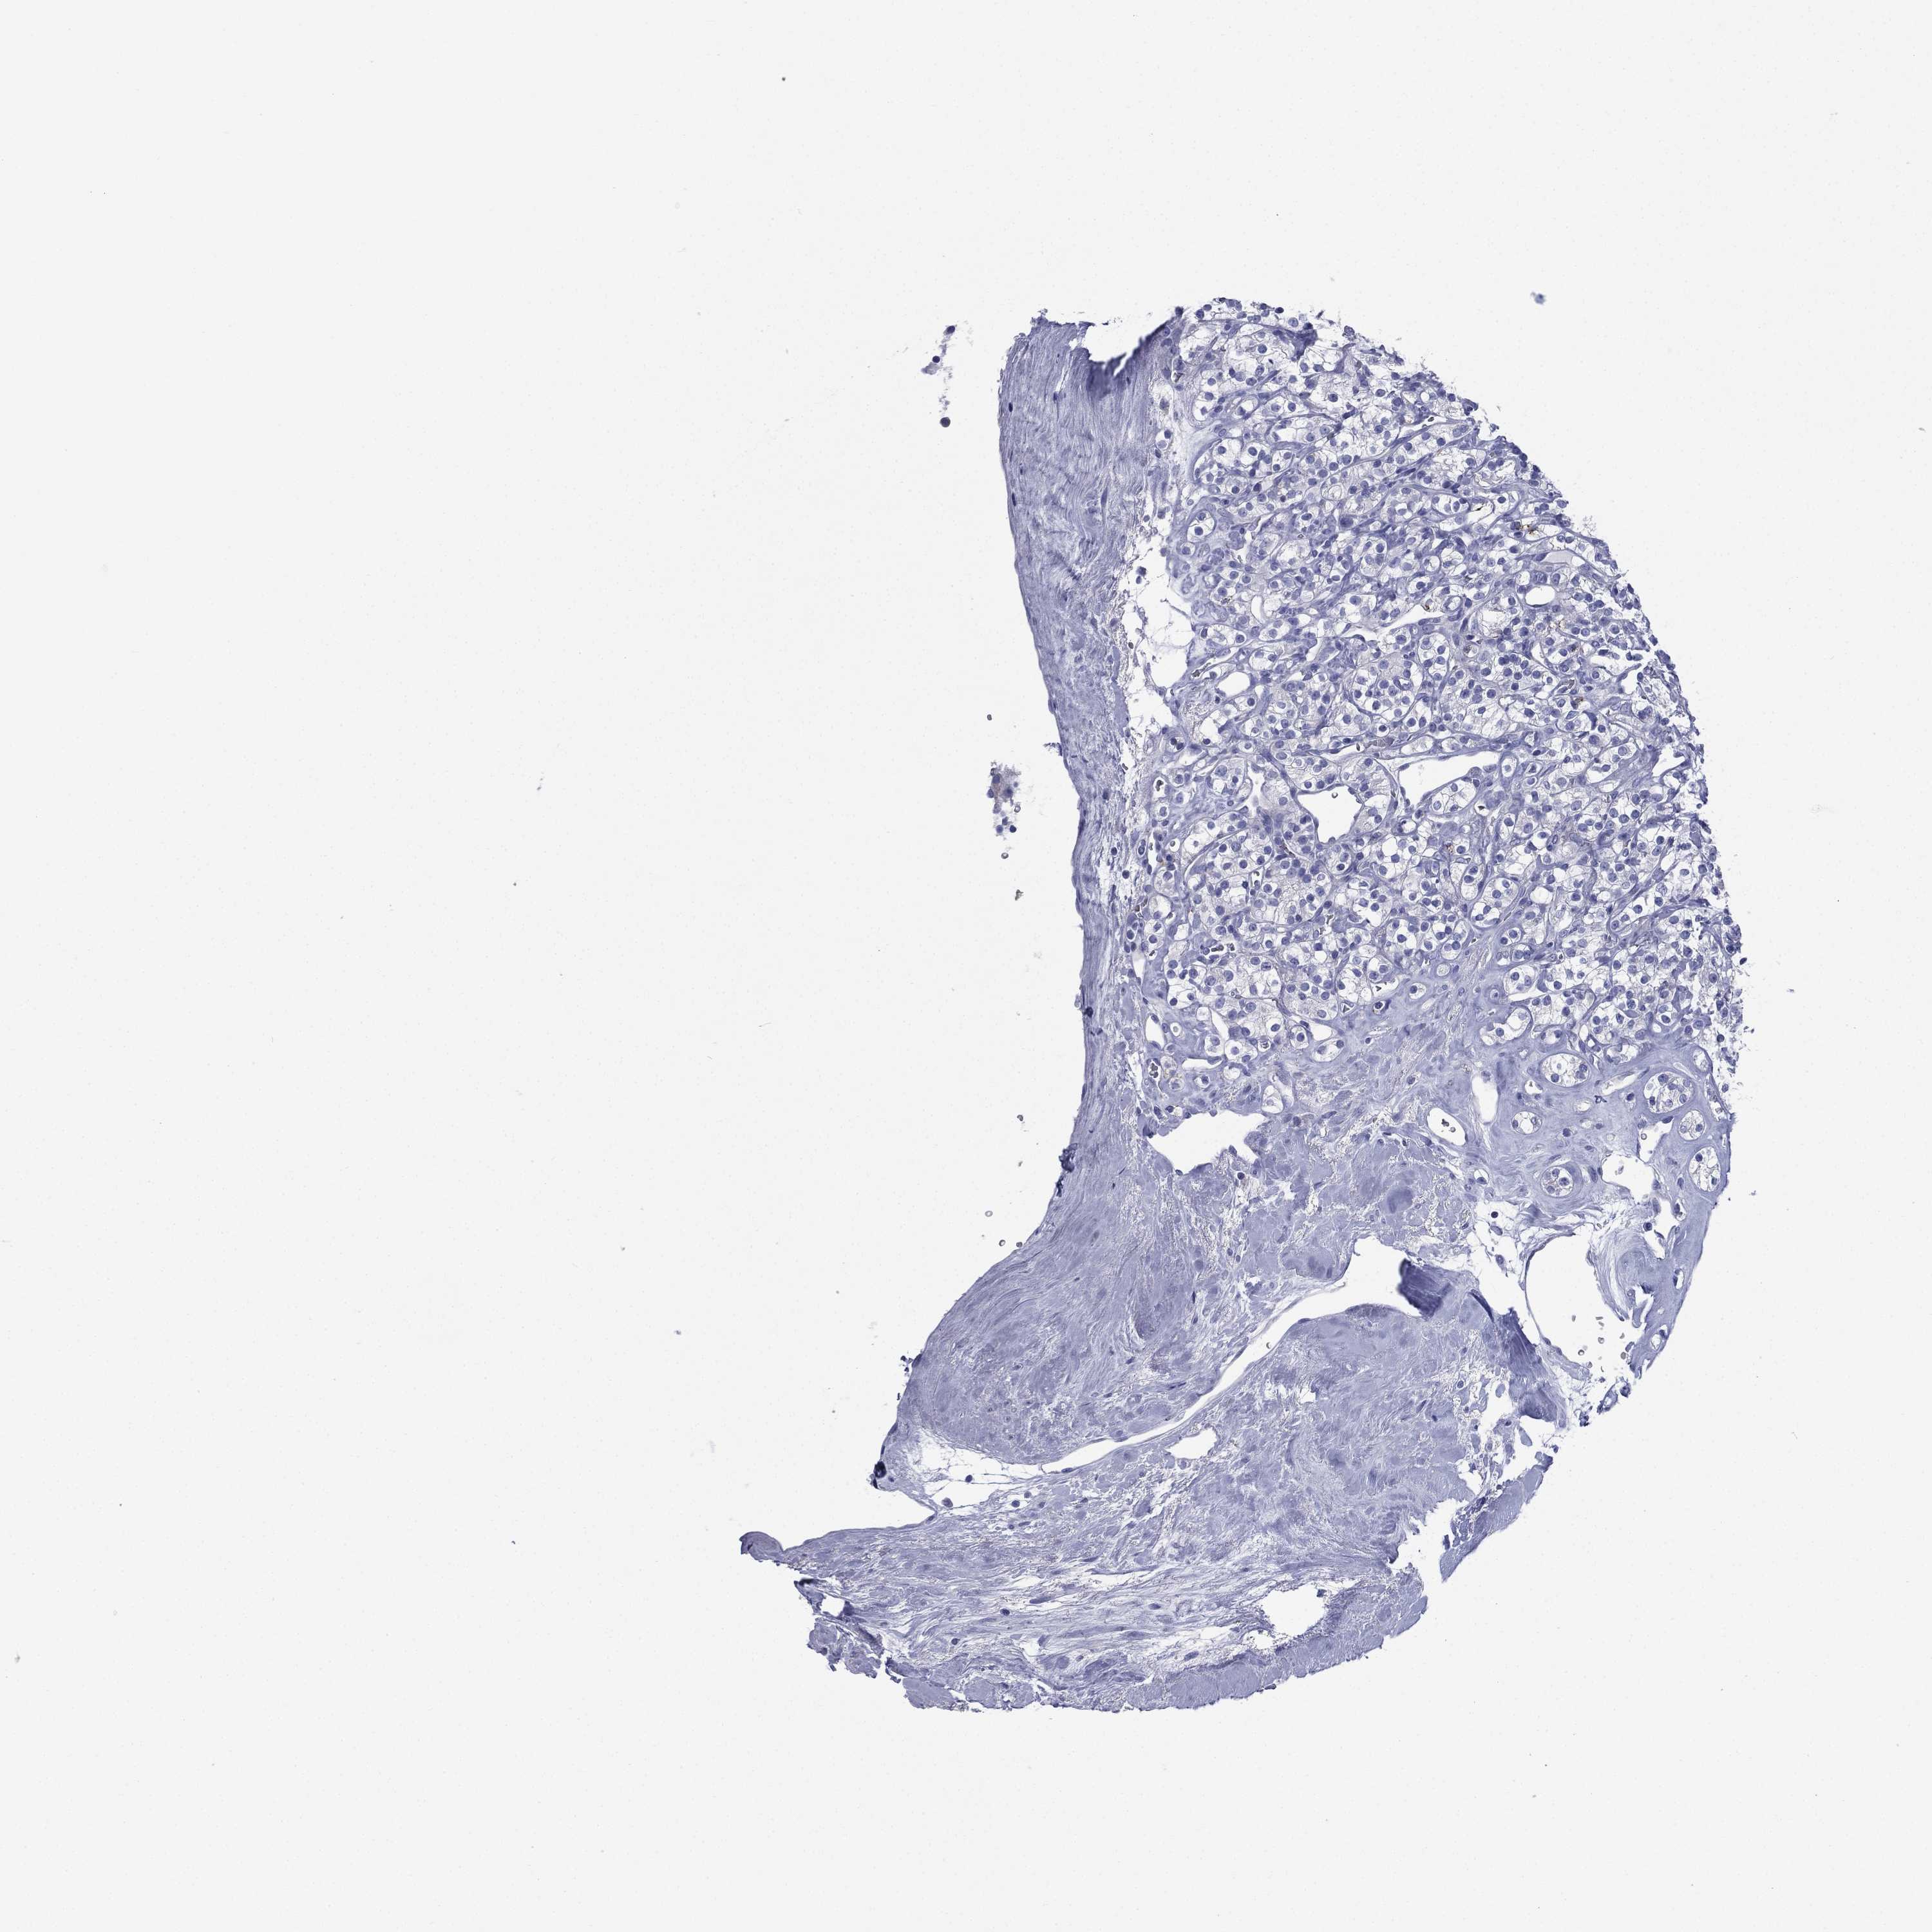

KIDNEY RENAL CLEAR CELL CARCINOMA (VALIDATION) - Interactive survival scatter ploti

The Survival Scatter plot shows the clinical status (i.e. dead or alive) for all individuals in the patient cohort, based on the same data that underlies the corresponding Kaplan-Meier plots. Patients that are alive at last time for follow-up are shown in blue and patients who have died during the study are shown in red.

The x-axis shows the expression levels (FPKM) of the investigated gene in the tumor tissue at the time of diagnosis. The y-axis shows the follow-up time after diagnosis (years). Both axes are complimented with kernel density curves demonstrating the data density over the axes. The top density plot shows the expression levels (FPKM) distribution among dead (red) and alive patients (blue). The right density plot shows the data density of the survived years of dead patients with high and low expression levels respectively, stratified using the cutoff indicated by the vertical dashed line through the Survival Scatter plot. This cutoff is automatically defined based on the FPKM cutoff that minimizes the p-score. The cutoff can be changed by dragging the vertical line or by entering a cutoff value in the square labeled "Current cut-off".

Under the Survival Scatter plot the p-score landscape (black curve; left axis) is shown together with dead median separation (red curve; right axis). Dead median separation is the difference in median mRNA expression between patients who have died with high and low expression, respectively. It is calculated as follows: median FPKM expression of dead patients with high expression - median FPKM expression of dead patients with low expression. This is intended to aid the user in visually exploring custom cutoffs and the associated p-scores and dead median separation.

Individual patient data is displayed and can be filtered by clicking on one or more of the category buttons on the top of the page. Categories describing expression level and patient information include: high, low, alive, dead, female, male and tumor stages. The scale of the x-axis can be toggled between linear and log-scale by clicking on the "x log" button. Mouse-over function shows TCGA ID, patient information and mRNA expression (FPKM) for each patient.

& Survival analysisi

Kaplan-Meier plots summarize results from analysis of correlation between mRNA expression level and patient survival. Patients were divided based on level of expression into one of the two groups "low" (under cut off) or "high" (over cut off). X-axis shows time for survival (years) and y-axis shows the probability of survival, where 1.0 corresponds to 100 percent.

FCER2 is not prognostic in Kidney Renal Clear Cell Carcinoma (validation)